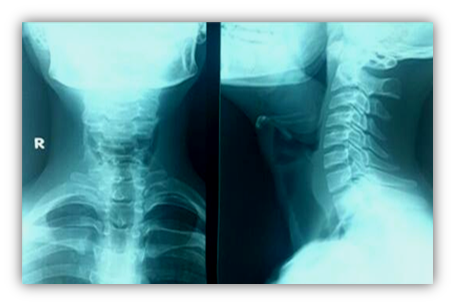

2. X ray lateral view showed oropharyngeal soft tissue shadow over the epiglottis

Then the decision of examination under general anesthesia and biopsy was taken (Figure 1 & 2).

Figure 1 Lateral soft tissue neck X-ray showing a sizable opacity (white star) projecting from the oropharynx into the hypopharynx causing significant encroachment upon the airways.